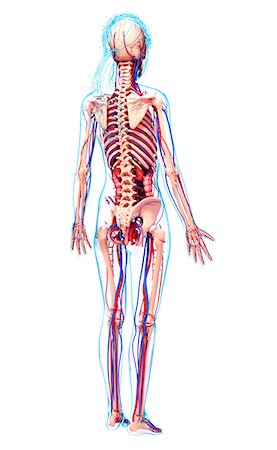

Femoral Artery And Pelvic Bones Stock Photos Page 1

Femoral Artery And Pelvic Bones Stock Photos Page 1

Femoral Artery And Pelvic Bones Stock Photos Page 1

Femoral Artery And Pelvic Bones Stock Photos Page 1